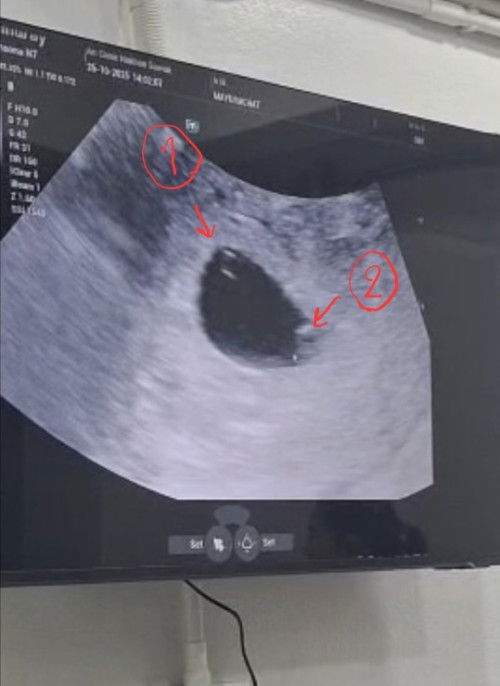

แม่ๆท่านไหน เคยพบถุงการตั้งครรภ์ 1 ถุง ถุงอาหาร 2 ถุงไหมค่ะ ทางนี้ ซาวตอน 5wk พบแบบในรูป แต่ถุงที่ 2 คุณหมอเห็นไม่ชัด นัดอีก 2 week ค่ะ แต่ถุงที่ 1 คุณหมอยืนยันว่าใช่แน่ๆ ถ้าจะเป็นแฝดจริงๆคุณหมอแจ้งไว้ว่าอาจจะมีความเสี่ยงเยอะ#ขอบคณสำหรับคำตอบล่วงหน้านะคะ